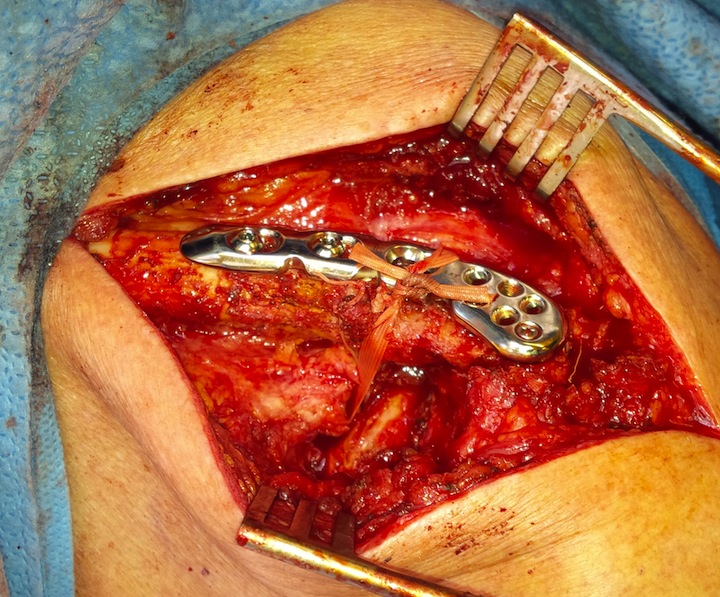

Dorsal locking plate with cerclage fibretape

Lazy beach chair

- divide deltoid-trapezius fascia

- expose clavicle

- clean and reduce fracture

- plate fracture

- expose coracoid

- suture anchor / suspensory fixation / cerclage tape or graft